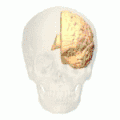

Cuneus

![]() Medial surface of left cerebral hemisphere. (Cuneus visible at left in red.) | |

The cuneus (from Latin 'wedge'; pl.: cunei) is a smaller lobe in the occipital lobe of the brain. The cuneus is bounded anteriorly by the parieto-occipital sulcus and inferiorly by the calcarine sulcus.